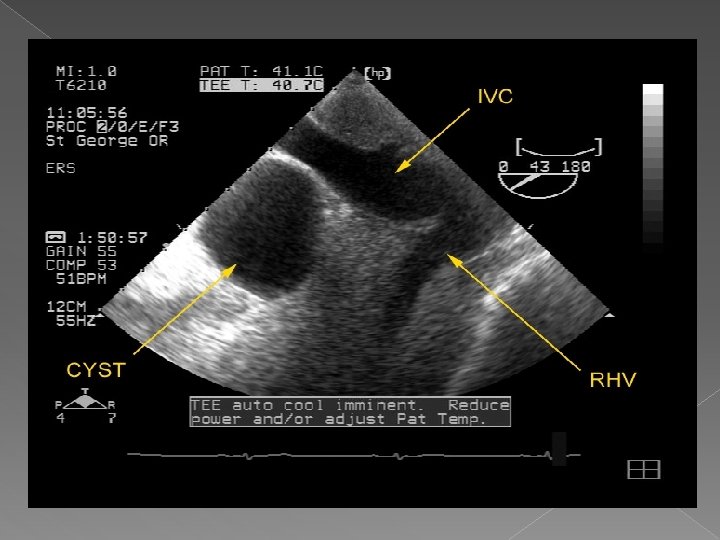

Chiste

Ultrasonografia : -uzuala, rapida, accesibila, informativa; -ideala pentru leziuni focale cu continut fluid; -tumorile solide sint mai greu de diferentiat. Scintigrafia: -rezultate bune in indentificarea leziunilor focale; -are valoare in aprecierea volumului si configuratia hepatica; -slaba specificitate.